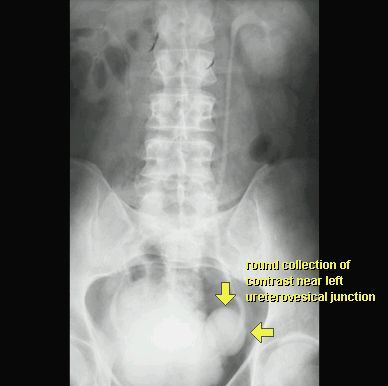

UCHYŁEK PĘCHERZA MOCZOWEGO

UROGRAFIA